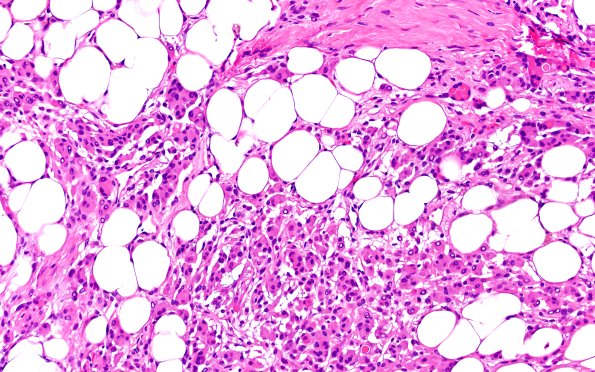

17C4 Meningioma, lipidized (Case 17) 20X

There is extensive lipidization of tumor cells as well as presence of secretory material. (H&E)